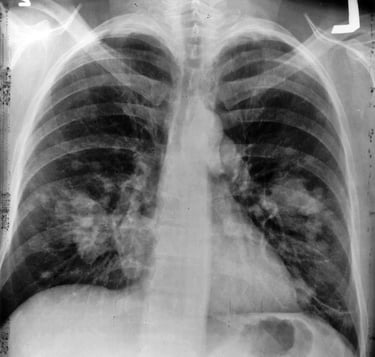

4. Tanısal Kartografi: Görüntüleme ve Moleküler Profilleme

Düşük Doz BT (LDCT): Tarama için altın standarttır. Nodül çapı 8 mm üzerine çıktığında ve kenar yapısı "spiküle" (dikenli) olduğunda, malinite riski Bayesyen eğride dikey bir tırmanışa geçer.

Radyolojik Görüntüleme Analizi

Görüntüleme BulgusuLR+LR-Analitik FarklılaşmaAkciğer Grafisi (Mass/Kitle)15.0 - 20.00.70Grafi negatifi kanseri dışlamaz (LR- 0.7 yüksek).Periferik Nodül (Düzensiz/Spiküle)10.0 - 12.00.15Adenokarsinom lehinedir; spikülasyon malignite olasılığını katlar.Hiler/Mediastinal Genişleme8.0 - 10.00.25Santral yerleşimli tümörler (Squamous/Small Cell) için kritiktir.Thorax CT (Kontrastlı)3.50.09Tanısal Altın Standart: Negatif bir CT, kanser olasılığını %90'dan fazla düşürür.MRI (Pancoast Değerlendirme)~30.0 (Staging)0.10Brachial pleksus ve vasküler invazyonu CT'den daha iyi gösterir.